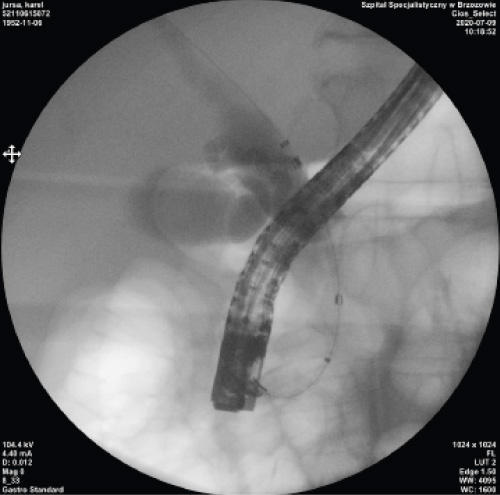

Case Presentation 1

To confirm my conclusions, I present a case of a patient, 68 years old, with a surgical pancreatic head tumor and gallbladder, in whom I implanted a BMCL stent:

1. Visible segmental stenosis of the distal part of the bile duct, visible gallbladder duct and gallbladder.

2. The BMCL stent kit, proximal, middle and distal markers visible.

3. Stent during deployment.

4. Deployed stent.

5. Endoscopic image of the stent during deployment - yellow marker under constant control.

6. Endoscopic picture of the deployed stent.